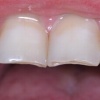

Ülemiste tsentraalsete lõikehammaste (intsisiivide) vahetumine. Retineerunud Intsisiiv

Ülemiste tsentraalsete lõikehammaste (intsisiivide) vahetumine. Retineerunud intsisiivid. Ülemised tsentraalsed esihambad lõikuvad orienteeruvalt 7-8-aastaselt. Enamasti lõikuvad samanimelised jäävhambad paaridena. Normaalne lõikumise järjekord 7, 5-aastselt: vt pilti